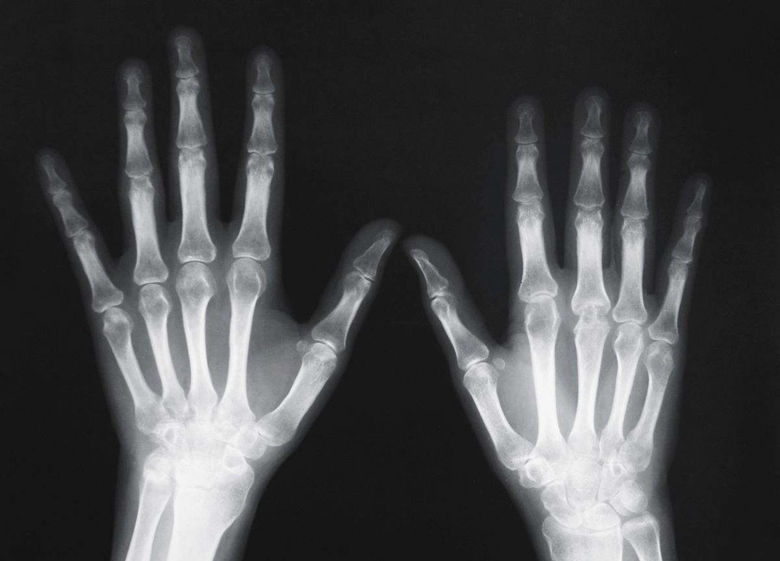

X线检查作为辅助检查方法之一。临床医学上常用的X线检查方法有透视和摄片两种。

摄片能使受检部位结构清晰地显示于X线片上,并可作为客观记录长期保存,以便在需要时随时加以研究或在复查时作比较。必要时还可作X线特殊检查,如断层摄影、记波摄影以及造影检查等。选择何种X线检查方法,必须根据受检查的具体情况,从解决疾病(尤其是骨科疾病)的要求和临床需要而定。X线检查仅是临床医学辅助诊断方法之一。